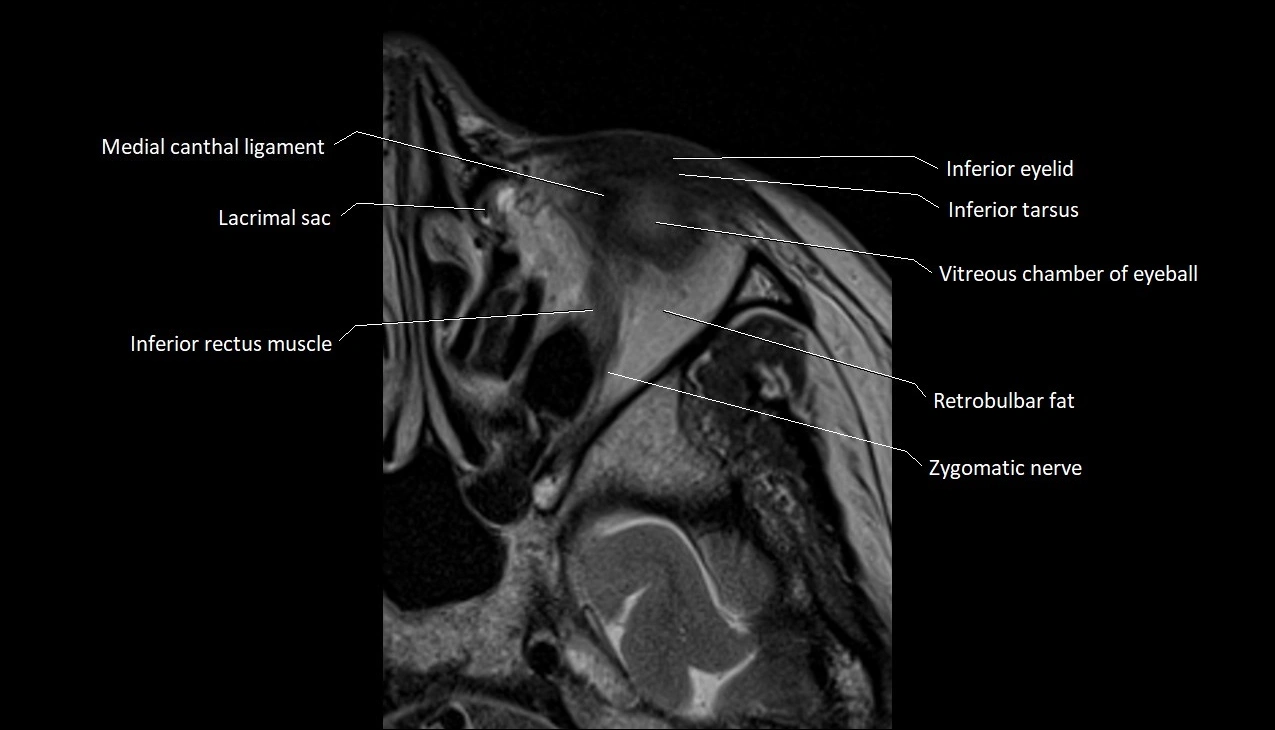

- Inferior eyelid

- Inferior rectus muscle

- Inferior tarsus

- Lateral canthal ligament

- Medial canthal ligament

- Retrobulbar fat

- Vitreous chamber of eyeball

- Zygomatic nerve